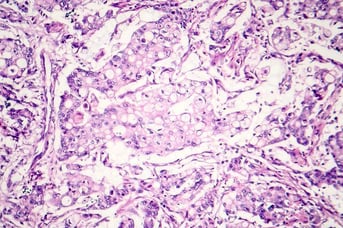

Tissue Biopsy Analysis

Support for all aspects of tissue biopsy analysis, including sample collection, a repository of 3M+ FFPE samples, global locations, and digital pathology solutions